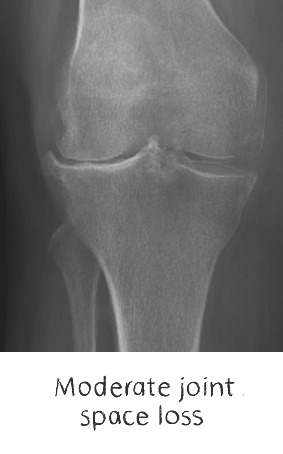

Plain film x-rays are taken to assess the joint

These are usually taken prior to your appointment. These help to confirm the diagnosis, assess the wear pattern and look for particular deformities. They can show old metalware and its position in the bone.